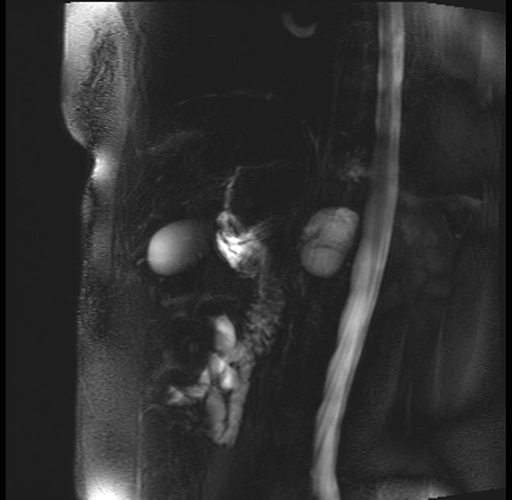

Imaging Analysis

Look through the patient's CT scan to identify any areas of concern for the necessary procedure.

Based on your CT findings, which issue(s) are present and would give reason for "planned slowing down moment(s)" in this case?